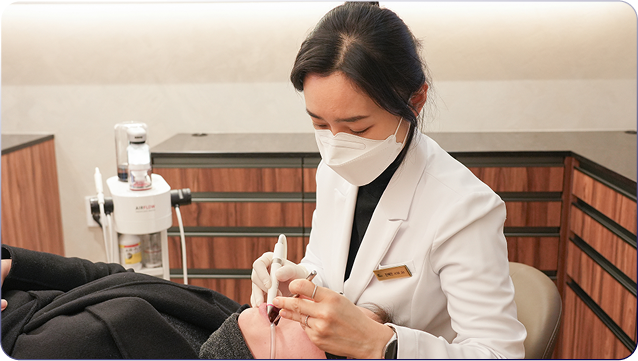

AI 구강검진 무제한

에어파우더 스케일링 무제한

치아미백 무제한

중간 인건비 없는 직접 진료

대표원장이 상담부터 치료까지

직접 담당해 중간 비용 절약 -